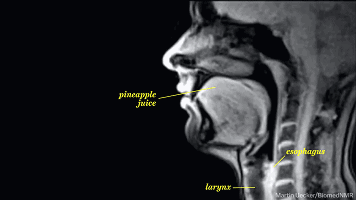

舌头

你以为你的舌头是受你自己只配的?

图样图森破,兴奋使你的舌头开始

躁动,这时候你的舌头已经在嘴里

开始跃跃欲试,要冲破禁锢的牢笼

所以不用我说你也知道要干什么了

随着舌头反映的出现,你的唾液开始

分泌增多,这会使你出现不自主的

吞咽动作。这回你知道自己为什么见到

美女就不停的咽口水了吧,自己想什么

心里没点数么

从下图可以看出两个人的舌头

都开始不老实了,接吻会加剧

兴奋,会使心跳速度进一步增加

呼吸也会更急促,全身的肌肉

开始出现不规则的收缩肌紧张